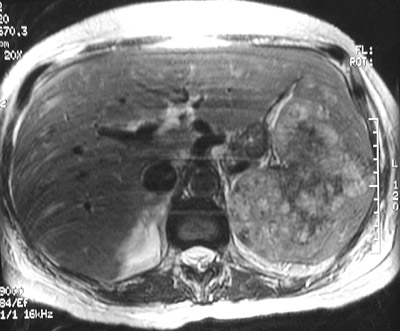

| There is a heterogenous splenic mass seen in the abdominal CT scan above. This large mass expands the spleen. Histologically, it was an angiosarcoma. In the T1 weighted MRI scan below can be seen areas of increased signal intensity characteristic for hemorrhage in a vascular neoplasm. A T2 weighted MRI scan is shown at the bottom in which the hemorrhagic-vascular areas appear darker. |